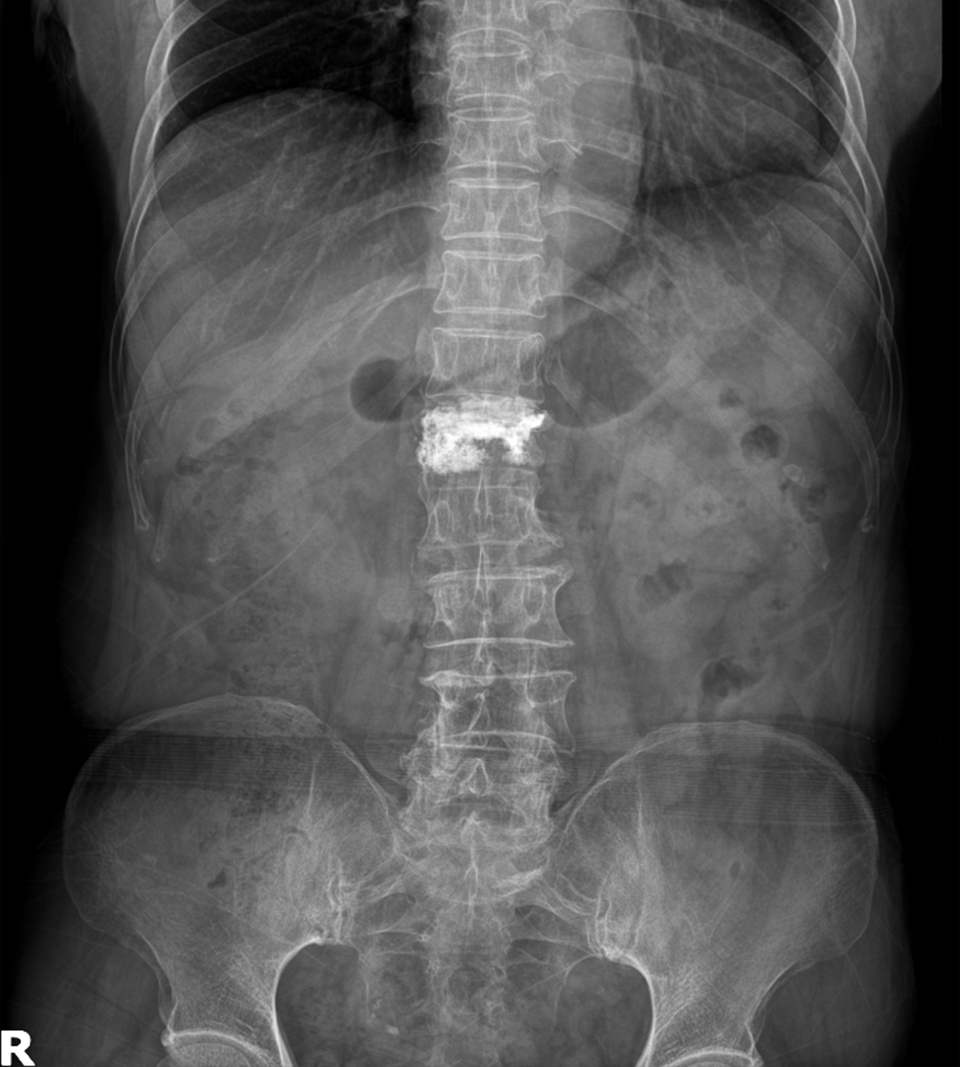

Compression Fracture

<수술전>

- 환자 동의하에 게시된 이미지입니다.

<수술후>